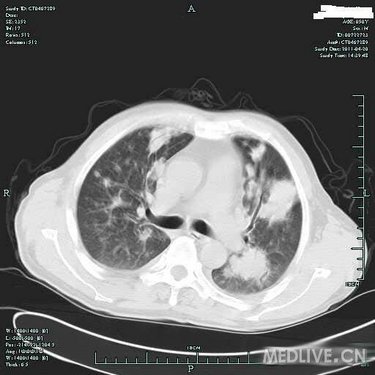

病史特点:患者于3月余前受凉后出现发热,体温为39.0摄氏度左右,伴咳嗽,为阵发性咳嗽,有咳痰,色白,有咽痛,无鼻塞及流涕,至当地诊所输液(具体不详)治疗后,效果不明显。于80天前入住当地医院,住院期间查胸部CT提示:双肺弥漫性结节影,纤支镜:双叶段粘膜轻度充血、水肿,痰找脱落细胞阴性,行左下肺经皮肺穿刺针吸细胞学未见异形细胞,曾予哌拉西林/他唑巴坦针、利福平、氟康唑针等治疗后,仍有反复发热,体温高达39.0摄氏度左右,发热时有气促感,无胸痛、头痛及心悸感。于2月余前至我院住院,CRP41.80mg/L,肺CT增强:两肺多发病灶,肿瘤不能排除,建议穿刺活检;气管镜检查:两侧支气管均通畅,未见新生物,气管镜刷片、肺泡灌洗液均未见肿瘤细胞;进一步行肺穿,肺穿刺涂片找到坏死组织,涂片未见肿瘤细胞,穿刺病理:(右)肺组织慢性炎伴坏死及淋巴组织增生;骨髓活检:造血细胞增生活跃伴散在T细胞浸润。予以出院带药HRE诊断性抗结核+SMZco治疗,患者用药不规则,仍有反复发热,最高达40摄氏度,伴畏寒,予退热药处理后热退,伴少量咳嗽及呕吐,无明显咳痰,复查肺部CT病灶对比前片增多、增大,为进一步诊治收住入院。

T 37.2℃,R 20次/分,P 82次/分,BP 114/79mmHg,神清,精神偏软,浅表淋巴结未及肿大,双肺呼吸音粗,未及明显干湿啰音,心律齐,瓣膜区未闻及病理性杂音,腹平软,无压痛及反跳痛,肝脾肋下未及,双下肢无浮肿,右上肢肌力IV级,握力差。

血常规(五分类)(病房):白细胞计数3.8×10E9/L,中性粒细胞(%) 84.8%,淋巴细胞(%) 4.7%,血红蛋白106g/L,血小板计数279×10E9/L。

血生化:总蛋白50.3g/L,白蛋白27.4g/L,球蛋白22.9g/L,白球蛋白比例1.2。 ANCA,MPO,PR3等检查未见明显异常。 癌胚抗原7.8ng/mL,神经元特异性烯醇化酶44.0。